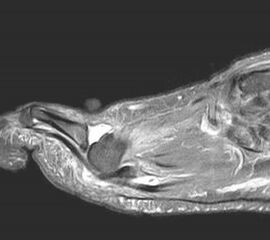

Die Überbelastung des Metatarsale II und III im distalen Bereich äußert sich in Druckschmerzen und Schwielenbildung plantar unter den Metatarsale II und III Köpfen (Abb. 1). Auch degenerative Veränderungen der plantaren Kapsel und der plantaren Platte der Metatarsophalangealgelenke treten auf, was zu einer Insuffizienz der Grundgelenke mit Subluxation oder Luxation der Kleinzehen führt (Abb. 2 und 3).

Bei den proximalen Überlastungsschäden mit Arthroseentwicklung im Übergang zur Fußwurzel am TMT II, seltener TMT III, beklagen die Patienten Schmerzen an der Fußwurzel vor allem beim Barfuß laufen oder in leichtem Schuhwerk. Auch kommt es häufig zu einer Affektion des N. peronaeus profundus, wenn ein dorsaler Osteophyt der tarsometatarsalen Gelenke vorliegt und der Nerv durch den Druck des Schuhs gegen die Knochenkante gedrückt wird. Die Kompression des Nervens ruft Beschwerden eines vorderen Tasaltunnelsyndroms hervor mit Dysästhesien oder Schmerzen im Nervenverlauf bis in den Interdigitalraum D1/2.